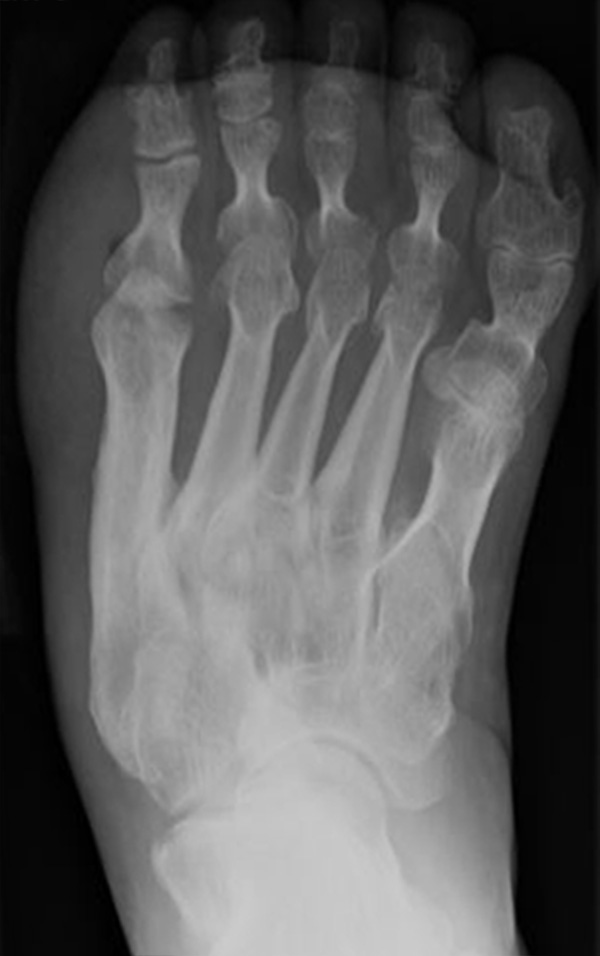

Abb. 8 a, b, c: Typ III Deformität mit prä- (a) und postoperativem Röntgenbild (b, c) mit Schrauben-Osteosynthese.